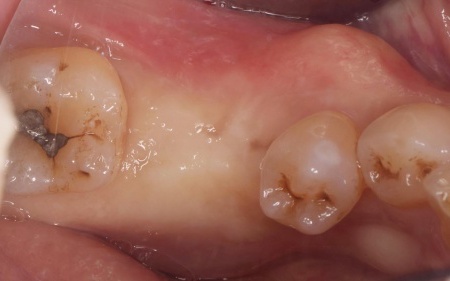

治療前

| 診断 | 拝見したところ、左下奥歯(第1大臼歯)が抜けており、見た目が気になるだけでなく奥歯でしっかりと噛むことが難しくなっていました。 このまま放置すると食事の際に支障が出たり、噛み合わせのバランスが崩れて残っているほかの歯に影響を及ぼしたりする可能性があります。 以上のことから、抜けた歯を補い見た目と噛む機能を回復させる治療が必要と診断しました。 |